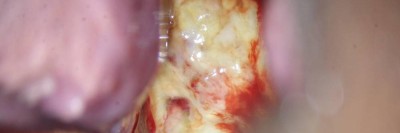

Ein Knubbel in der Wange – an welche Diagnose denken Sie?

Nach wiederholten Besuchen bei Kinder-, HNO- und Zahnärzten steht nun die 11-jährige Patientin vor Ihnen. Sie leidet seit zwei Jahren unter belastungsabhängigen Schmerzen beim Kauen. Nachdem eine vorausgegangene Sonographie und ein vergrößerter Lymphknoten eine Raumforderung im M. masseter vermuten lassen, sehen Sie nun diese MRT-Bildgebung.